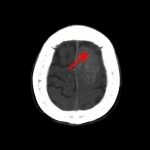

断層撮影